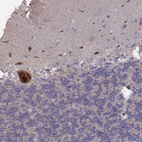

Immunohistochemical staining of human cerebral cortex shows strong cytoplasmic positivity in neuronal cells.